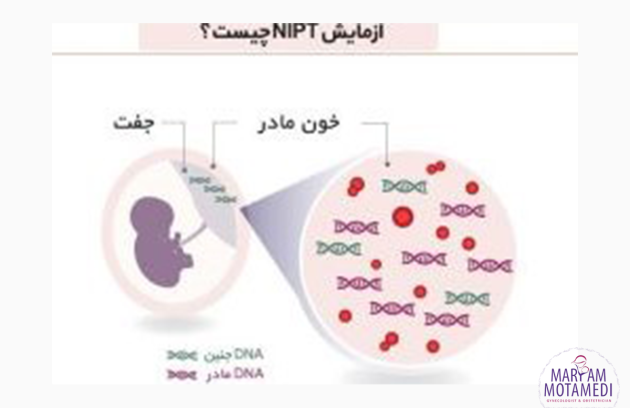

آزمایش سل فری چیست؟